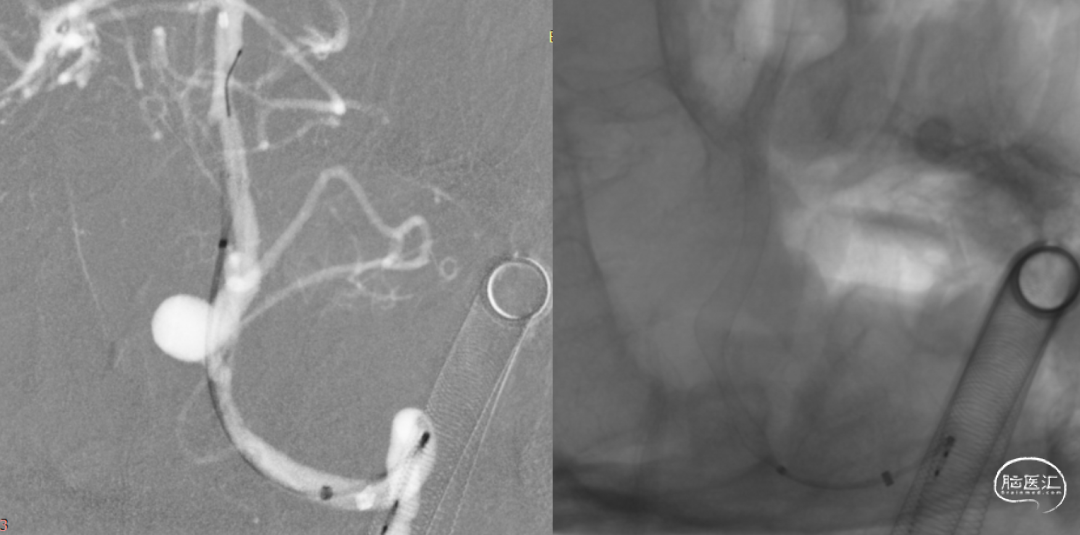

J-Tube™打开过程-整体显影性能良好。

J-Tube™血流导向密网支架打开过程。

动脉瘤近端血管狭窄

回收密网支架重新释放,狭窄依然存在。

释放J-Tube™血流导向密网支架。

释放支架后造影,可见血液滞留明显。